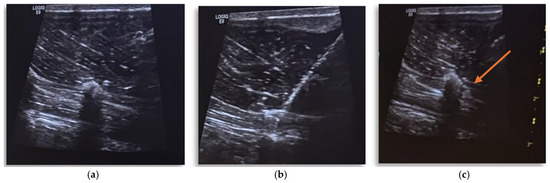

Anesthetic Management